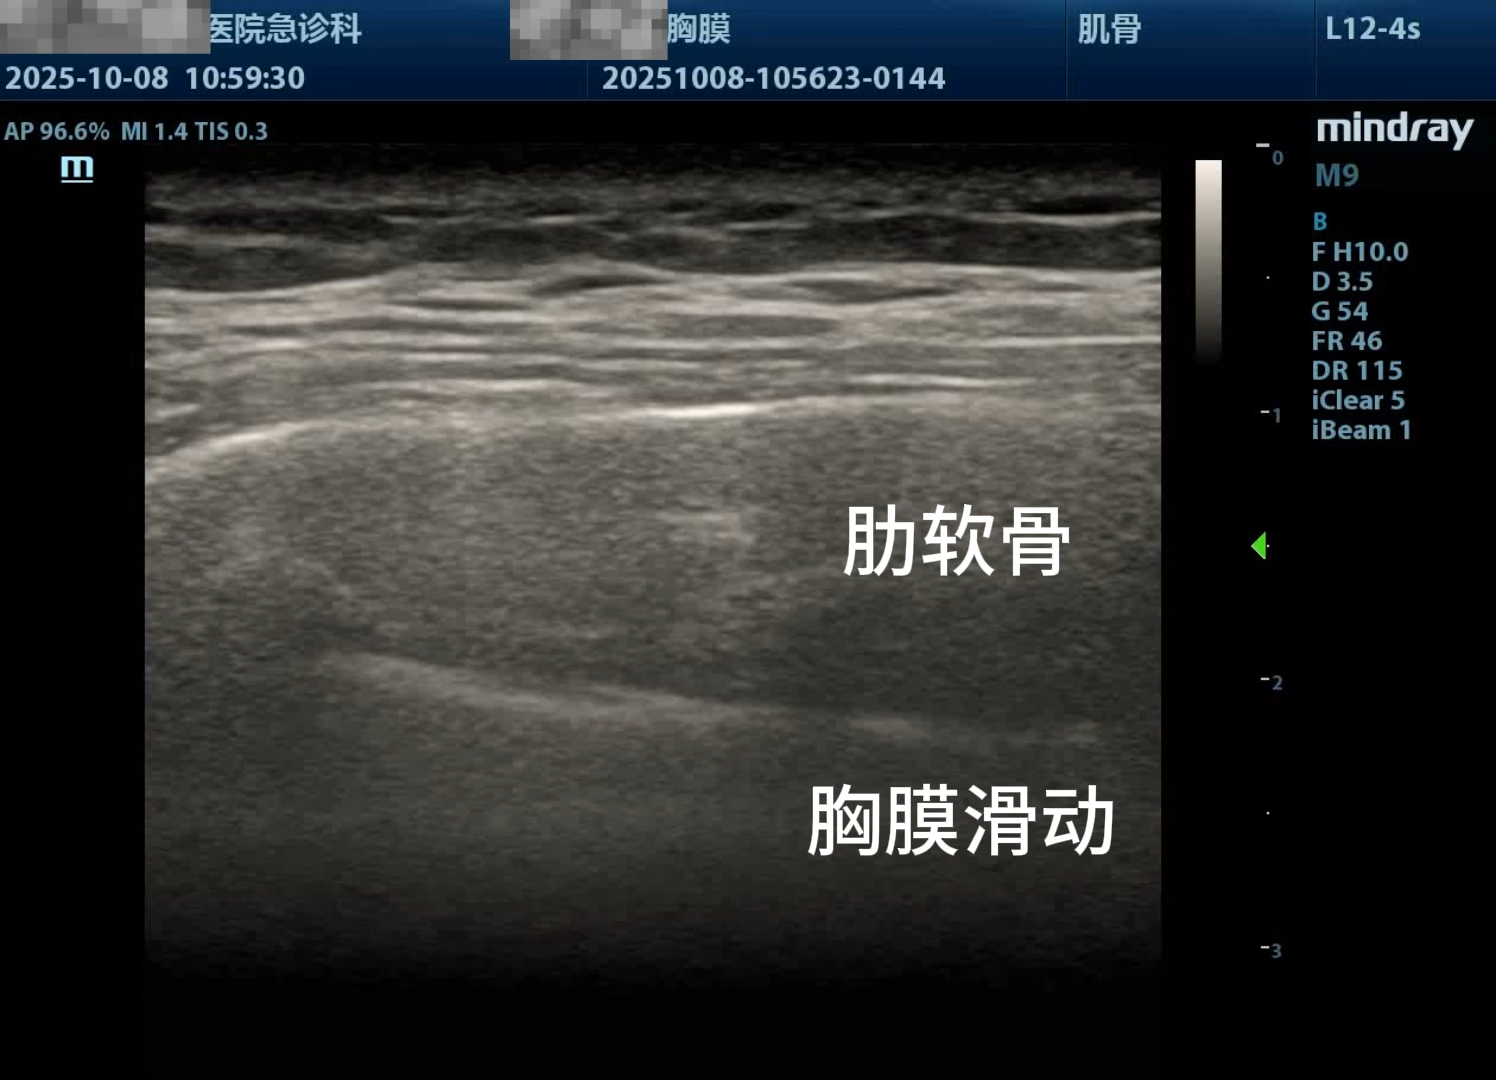

月叔打怪兽急诊科医师

昨天值班遇到的一例晕厥病例,差点漏诊,而最终的解法,始于最简单而质朴的查体。国庆中秋双节的最后一天,8号的早上8点,抢救室床旁晨交班,病人依旧是多而重,交到6床,一个刚入室不久的病人,准备去做CT,夜班医师汇报病史:69岁男性,本次因“头晕伴一过性晕厥1小时”为主诉入抢,1小时前于高铁站因即将赶不上高铁走路快时突发头晕,伴一过性晕厥,约3-4分钟后清醒,清醒后诉今晨未吃早餐,已服用降压药物,仍有头晕头痛、四肢乏力等不适,无胸闷胸痛,无畏寒发热,无咳嗽咳痰,无恶心呕吐,无肢体麻木,无视物模糊等不适,路人拨打120送至我院急诊就诊。既往高血压,长期服用氨氯地平+福辛普利,血压控制一般;糖尿病,长期